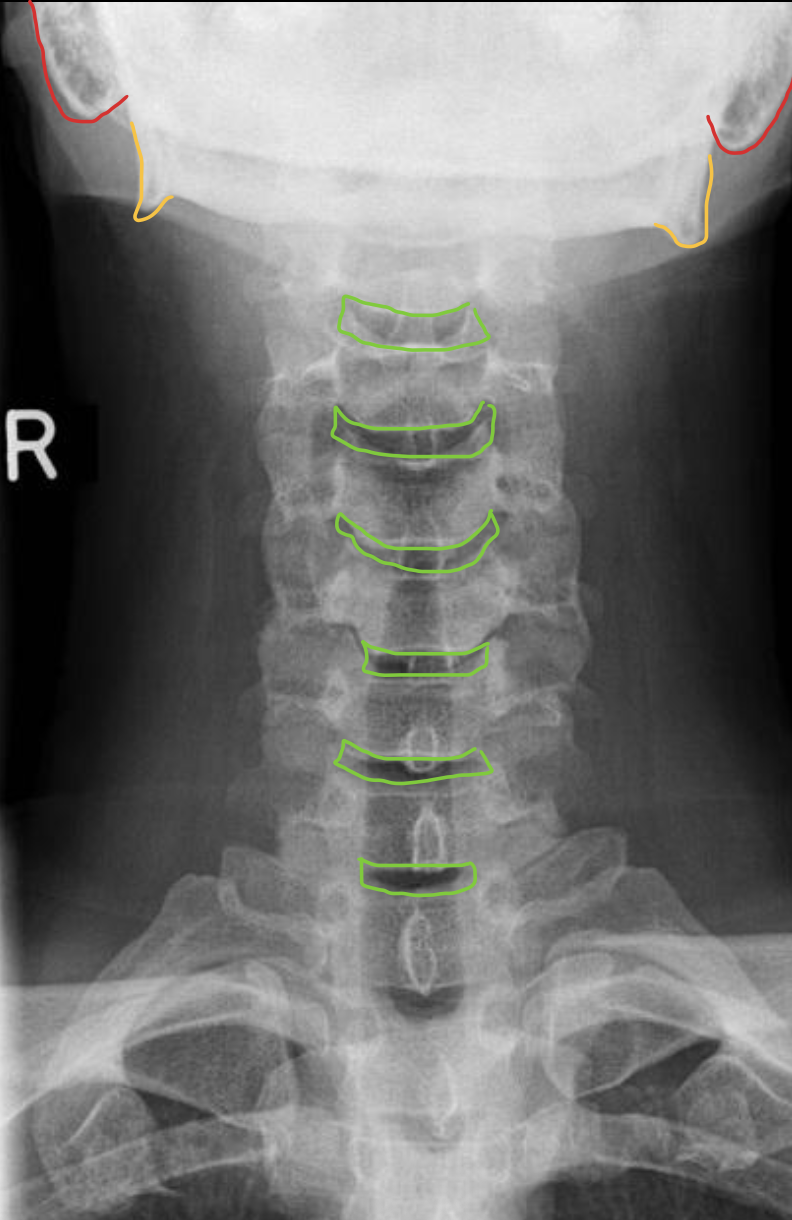

乳突气房

Mastoid air cells

下颌角

Angle of mandible

椎间隙(Intervertebral Disc space)

IVD space